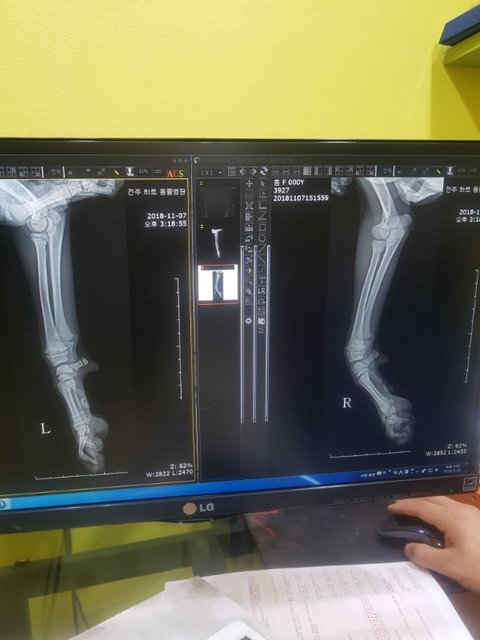

검진 다녀왔습니다

다행히 골절은 아니라고 합니다.

영양실조..

영양부족으로 구루병이 생긴듯 하다고 하시네요